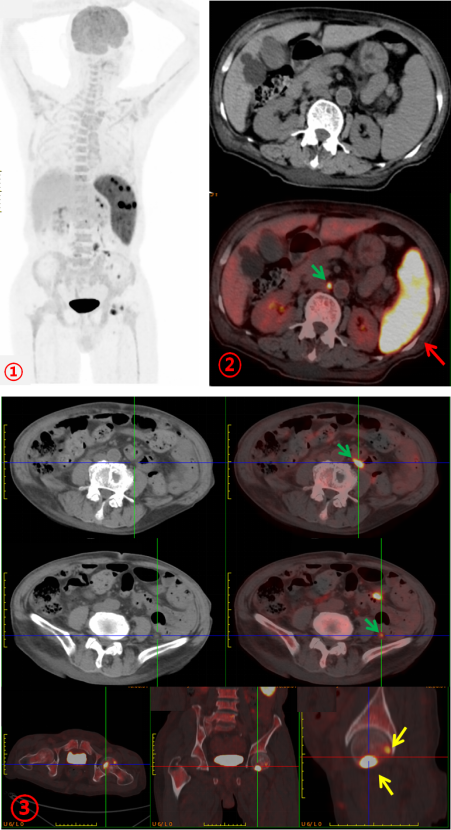

為進(jìn)一步明確病情,完善PET/CT檢查。PET/CT示:脾臟彌漫性增大伴FDG代謝明顯不均勻增高(SUVmax約22.3;圖1、2,紅箭),腹膜后及腹腔內(nèi)多發(fā)FDG代謝增高結(jié)節(jié)(SUVmax約8.8;圖1、2、3,綠箭),全身多發(fā)骨骼FDG代謝增高,左股骨頭為著,(SUVmax約11.7;圖1、3,黃箭),骨骼未見明顯破壞。PET/CT診斷為淋巴瘤?;颊唠S后完善骨髓活檢,病理診斷為:小B細(xì)胞淋巴瘤。